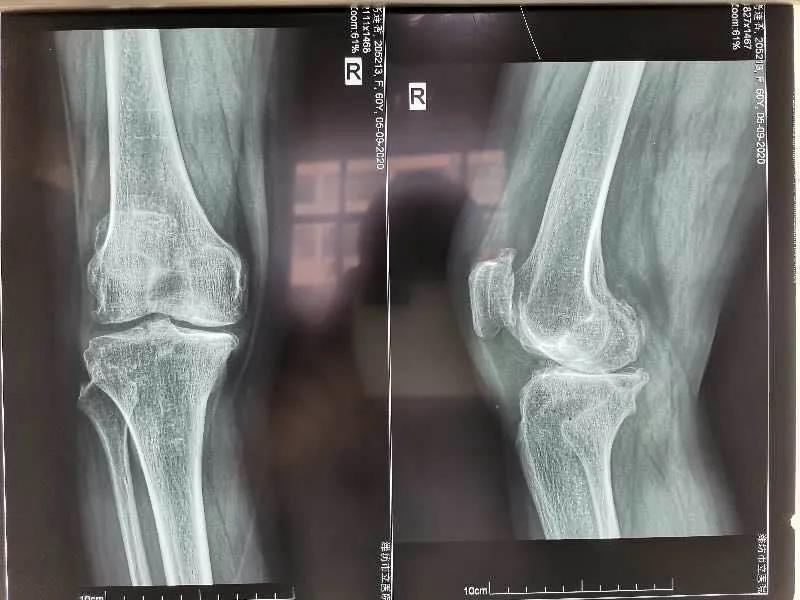

手術前